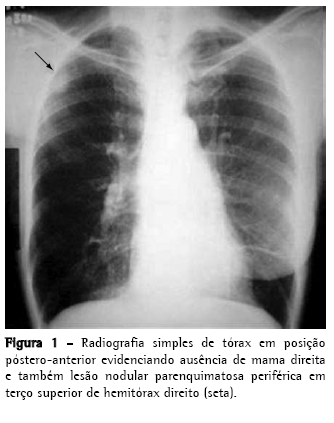

Paciente do sexo feminino, 60 anos, branca, em menopausa há 14 anos, é encaminha devido à presença de nódulo pulmonar à radiografia de tórax (Figura 1) diagnosticado no seguimento pós-operatório por neoplasia de mama. Trata-se de uma paciente que tem como antecedente pessoal a realização de mastectomia total à direita e linfadenectomia axilar ipsilateral há 3 anos por carcinoma ductal invasivo (diagnosticado por core biopsy) de 45 mm em seu maior eixo, grau nuclear II e estádio IIB (T2N1Mx). Submetida também à hormonioterapia (tamoxifeno 20 mg/dia) e quimioterapia (ciclofosfamida + metrotexate + 5-fluorouracil: quatro ciclos neoadjuvantes e seis ciclos adjuvantes), assim como a radioterapia adjuvante (dose total de 50 Grays por cinco semanas). Negava sintomas pulmonares, febre e emagrecimento.